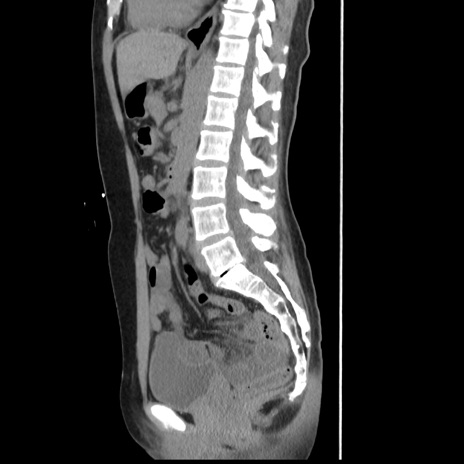

症例10(矢状断像)

【症例】 50歳代女性

【主訴】 腹痛

【現病歴】前日生レバーを食べた。今朝に排便あり。 昼前に突然発症の腹痛を生じ、当院救急外来を受診した。

【既往歴】 子宮筋腫にてで子宮全摘後

【身体所見】 意識清明、腹部:平坦、軟、下腹部やや左を中心に圧痛・反跳痛あり、筋性防御あり

【データ】WBC 7800、CRP 0.07